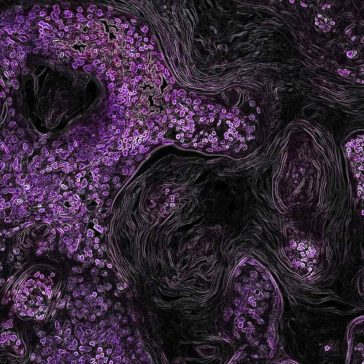

Unraveling the Impact of Tumor Microenvironment on DLBCL Prognosis and Treatment

Understanding the Tumor Microenvironment in Diffuse Large B-Cell Lymphoma (DLBCL) Introduction Diffuse large B-cell lymphoma (DLBCL) is a complex disease, both in terms of its genetic makeup and the role of the tumor microenvironment (TME) in its development and progression. Research into these aspects of DLBCL has shown great promise in terms of developing more […] More